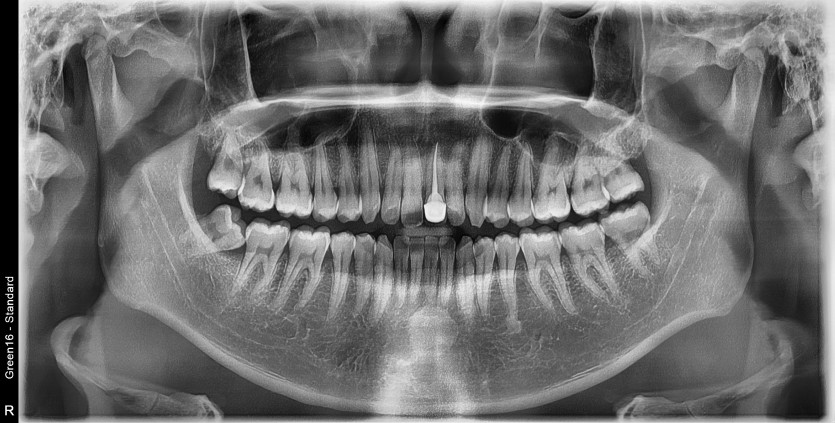

#18,48 사랑니 발치

구강 외과 전문의가 당일 발치했습니다.